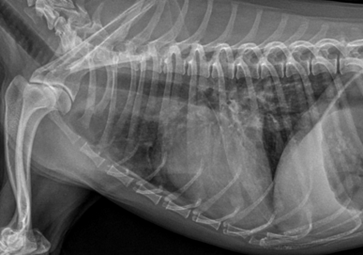

퇴원 당시 방사선 사진 볼까요?

완벽하게 폐부종이 사라지지는 않았네요? 아이의 경우 병원에서는 워낙 밥을 잘 먹지 않고

예민했던 아이이기 때문에 무리한 입원보다는 응급 상황만 해소 후 퇴원 후 내원약으로 관리해보기로 하였기 때문입니다!